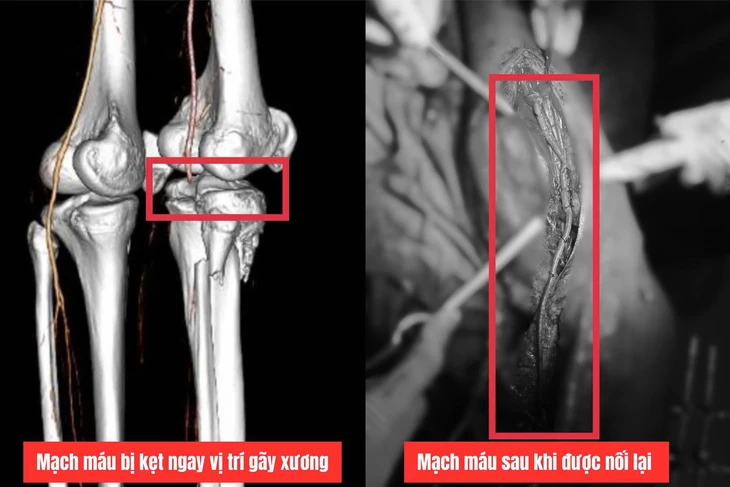

Resultaten från datortomografin visade att patienten hade förlorat signal till poplitealartärerna och de främre tibialartärerna, vilket förutspådde risken för amputation av höger ben på grund av långvarig ischemi i extremiteten.

Läkaren upptäckte att en artär som fastnat mellan frakturstället, a. poplitea och a. tibial främre var krossad och blockerad i nästan 20 cm.

Teamet bestämde sig för att utföra en så kallad "poplitealarterie bypass", där man tog ett 40 cm långt segment av vänster benven för att ersätta den skadade poplitealartären och återställde blodflödet från låret till vaden.

Den skadade artären ersattes med en ven från det återstående benet - Foto: Quang Tri General Hospital